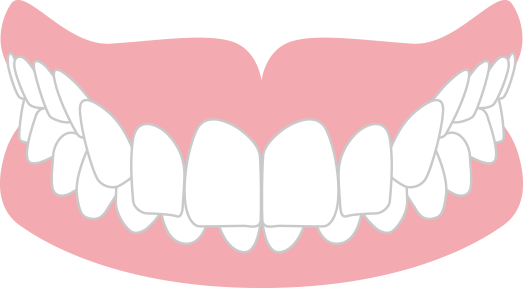

出っ歯 上顎前突

上の歯が前方に突出している状態。

唇が閉じにくく、口呼吸・ポカン口の原因になります。また上唇が前方に突出したお顔つきになります。重度の出っ歯の場合は矯正歯科治療が保険適用になります。